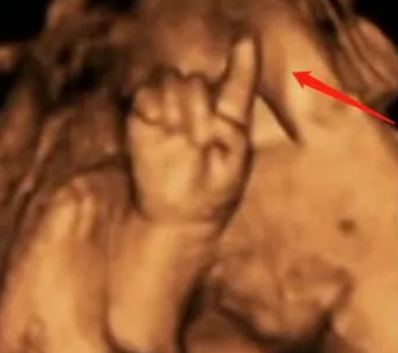

瞧瞧下图,有位孕妈妈做产检的时候,发现胎儿竟然在肚子里掰手指“算数”

医生开玩笑的说:北大清华的料!

网友看了这神奇的图片,也纷纷送上祝福:希望宝宝健健康康!但也不免好奇,到底是啥检查,看得这么清晰呢?

孕妈妈做的检查其实是胎儿系统超声(四维彩超),这是孕中期特别重要的一项B超检查。主要目的是筛查胎儿结构畸形,预防出生缺陷。